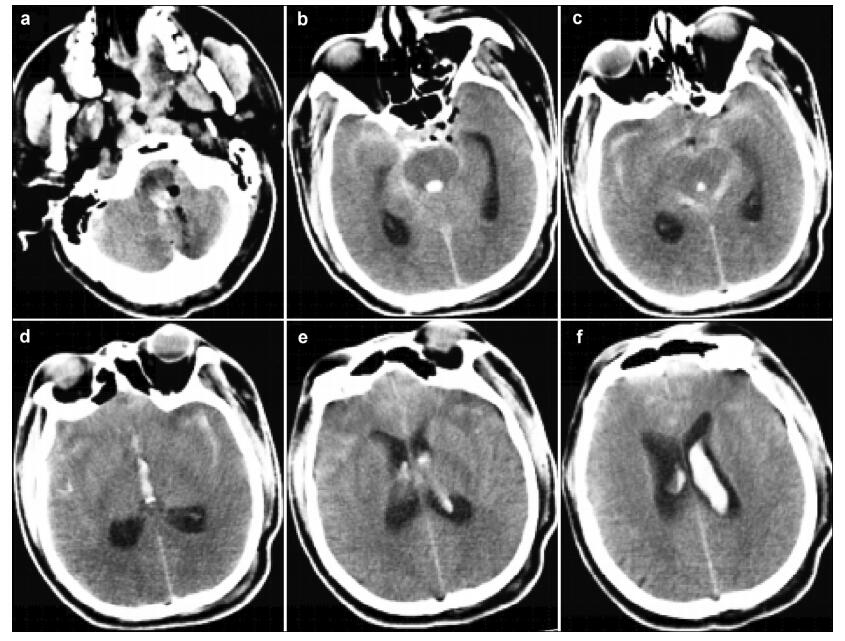

The patient received intensive care, his con sciousness recovered rapidly post-surgery, and his breathing was spontaneous. Pale bloody cerebrospinal fluid was seen slowly flowing through the drainage tube. Nevertheless, the patient’s stable condition was not maintained. At 4 hours post-surgery, the patient’s blood pressure rose to 180/110 mmHg. He was immediately treated with nitroglycerin. However, he developed an intense headache and suspected epileptic seizures and lost consciousness. Subsequently, his oxygen saturation began to decrease. His Glasgow Coma Scale (GCS) score dropped to 6/15 from a previous 15/15. His pupils remained equal and reactive with a 3-mm diameter. Hemorrhagic cerebrospinal fluid was gradually seen emanating from the drainage tube in the following 3 minutes. The patient received emergency tracheal intubation and ventilator-assisted breathing because of the loss of spontaneous breathing and the associated decreased oxygen saturation. An emergency CT scan showed an extensive intracranial subarachnoid hemorrhage and fourth and left lateral ventricular hemorrhage (Figures 4a-4d). No definitive emergency surgical procedure could be performed at that time. Unfortunately, the patient’s prognosis was very poor. Considering the patient’s condition was not consistent with survival, the family members were appropriately informed. The family consented to a withdrawal from further treatments and the patient died with his family at his bedside. His family refused an autopsy.

| Figure 4 (a–f) Postoperative emergency CT scan showing extensive intracranial subarachnoid hemorrhage, and fourth and left lateral ventricular hemorrhage. |